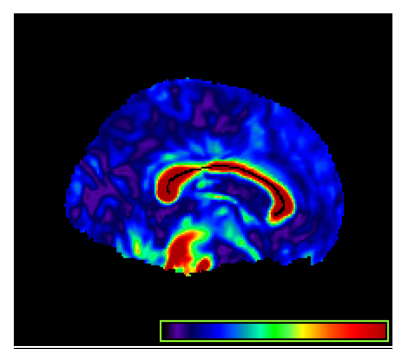

The DTI data were processed by two key steps including a weighted least squares estimation method Basser et al. [3]; Zhu et al. [50] to construct the diffusion tensors and a FSL TBSS pipeline Smith et al. [38] to register DTIs from multiple subjects to create a mean image and a mean skeleton. Speciffically, maps of fractional anisotropy (FA) were computed for all subjects from the DTI after eddy current correction and automatic brain extraction using FMRIB software library. FA maps were then fed into the TBSS tool, which is also part of the FSL. In the TBSS analysis, the FA data of all the subjects were aligned into a common space by non-linear registration and the mean FA image were created and thinned to obtain a mean FA skeleton, which represents the centers of all WM tracts common to the group. Subsequently, each subjects aligned FA data were projected onto this skeleton. We focus on the midsagittal corpus callosum skeleton and associated FA curves from all subjects, see Figure 1 (Right) for some selected subjects. The corpus callosum (CC) is the largest fiber tract in the human brain and is a topographically organized structure, see Figure 7 (Left). It is responsible for much of the communication between the two hemispheres and connects homologous areas in the two cerebral hemispheres. It is important in the transfer of visual, motoric, somatosensory, and auditory information.